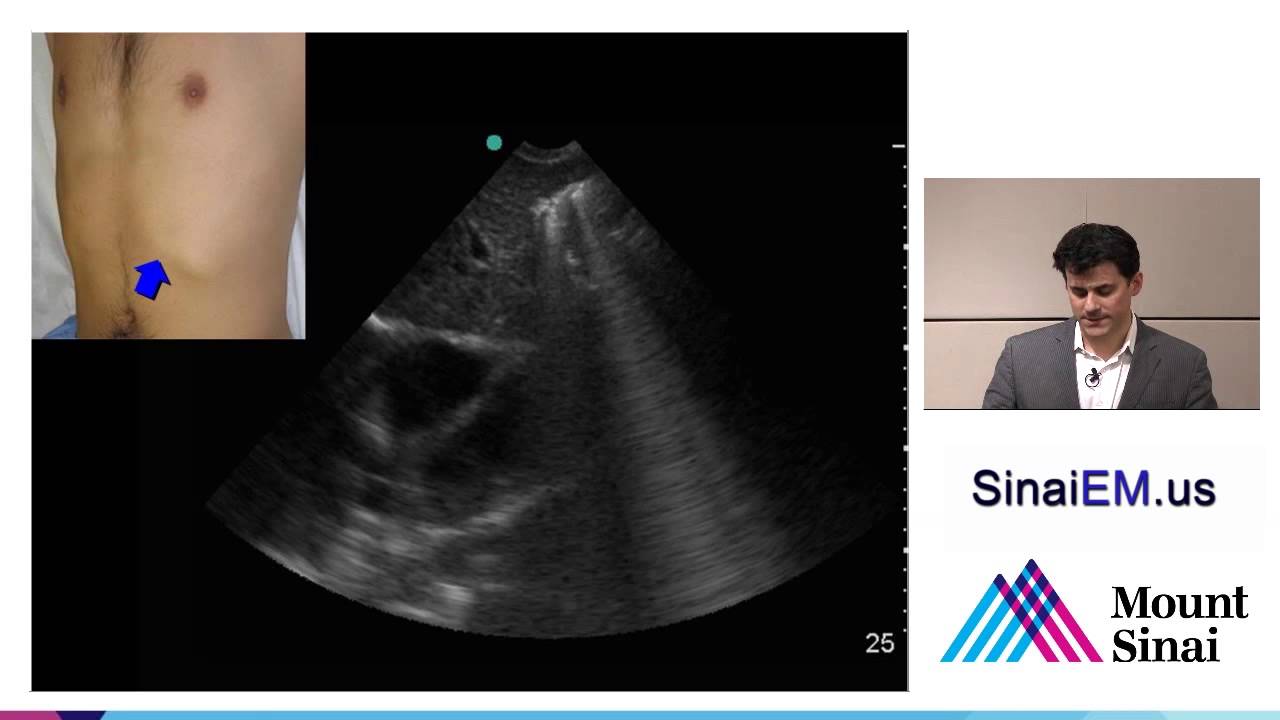

Ultrasound assessment of the abdominal aorta including aortic aneurysm, by Bret Nelson, MD, RDMS, FACEP.

Department of Emergency Medicine, Mount Sinai School of Medicine

www.SinaiEM.us